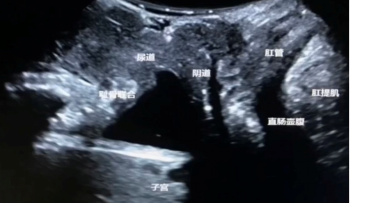

超声图像展示

盆底二维超声图像

通过先进的高清3D超声,全面观察评估整个盆底支持结构及盆腔内器官的形态与功能。

●盆底超声是将超声探头置于会阴部,通过观察比较患者静息、缩肛和Valsalva状态下盆腔脏器的位置变化,从而评估盆腔内脏器有无脱垂及盆底肌肉的损伤程度。盆底超声只需检查前排空大小便,无需其它特殊准备。盆底超声具有实时,直观,高效等优点,成为目前诊断盆底功能障碍首选的影像学方法,可以在患者出现临床症状前及时发现盆底结构的形态学改变,进行早期诊断。